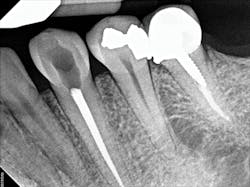

To determine whether tooth No. 21 or No. 22 was the issue, two periapical radiographs were taken. However, the results were inconclusive (figures 2–4). With clinical testing and 2-D radiographs providing no smoking gun, it was decided to use limited field-of-view CBCT (Carestream Dental CS 9000C 3D) on the region. CBCT revealed that tooth No. 22 was abscessed and a fair amount of the apical bone was completely gone (figures 5 and 6). In fact, since the time the pain began and when the patient presented at the practice, the tooth had abscessed at an alarming rate and was now considered an emergency situation.

Figure 2: A periapical radiograph showing a suspicious area (i.e., radiolucency) approximating the apex of tooth No. 20, as well as the defective distal occlusal restoration on tooth No. 21

Figure 3: A periapical radiograph showing tooth No. 22 with a radiolucency near the apex, which looked small relative to the areas on Nos. 20 and 21. There is also distortion of the appearance of the mental foramen in the area.